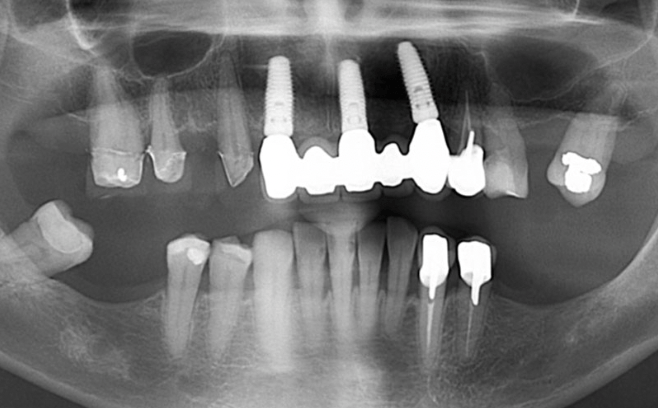

Un implant dentaire désigne la « racine artificielle » d’une dent : sous forme de vis biocompatible (titane ou zircone), il est inséré dans l’os de la mâchoire pour remplacer la racine d’une dent manquante. Sur cette base, un pilier prothétique est fixé, puis une couronne ou un bridge vient restaurer la dent perdue.

Chez nous, chaque intervention d’implantologie à Baie-Mahault commence par une planification rigoureuse: bilan radiologique, évaluation osseuse, contrôle parodontal — tout est pensé pour assurer un résultat fiable et esthétique.

1. Diagnostic et planification

Avant toute intervention, un examen médical complet est réalisé : le parodonte doit être sain, le volume osseux évalué — parfois grâce à un scanner 3D.